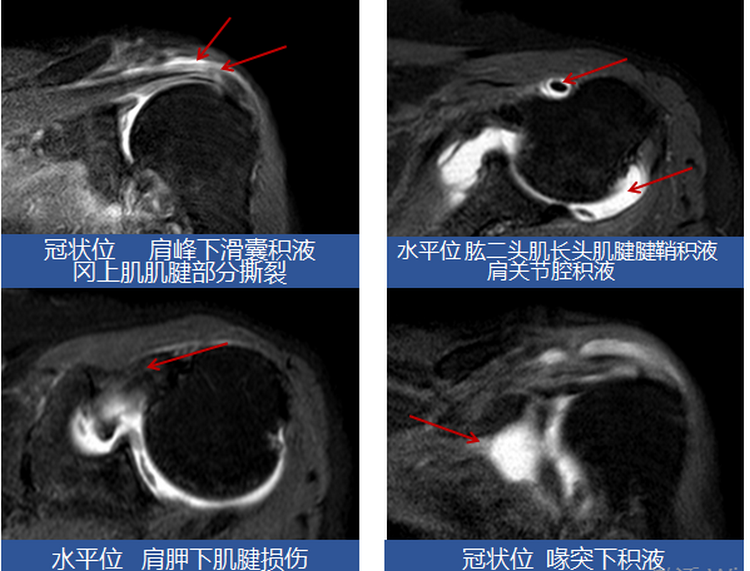

入院后经专科查体及辅助检查后,考虑该患者为肩关节半脱位合并肩袖损伤、左侧肱二头肌长头肌腱腱鞘炎。诊断明确后,为该患者制定康复目标(强化左侧肩关节稳定性、缓解左肩关节疼痛、提高肢体实用性),并根据该目标为患者制定了个体化康复治疗方案。经一个疗程的治疗,患者左肩关节疼痛较前减轻,夜间睡眠质量也得到显著改善,左上肢实用性有所提高,可以拿馒头送到嘴里,达到患者目标,出院回家。

肩关节半脱位、肩峰撞击综合征、肩手综合征、痉挛/挛缩/粘连性关节炎、周围神经病变、肩袖损伤、肱二头肌长头肌腱腱鞘炎。

包括疼痛性质评价、肩关节外观、肩关节活动、肩部超声、肩关节磁共振、心理评估。